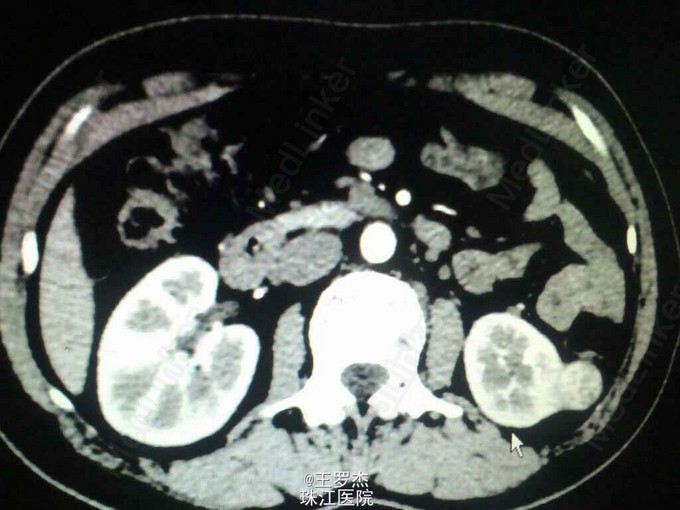

主诉:发现左肾及肾上腺占位3年 患者3年前因VHL综合征行常规体检时CT提示左肾低密度结节影,边界模糊,大小1.2x1.5cm,左肾上腺类圆形结节影,大小0.8x1.0cm,增强扫描明显强化。 既往史:12年前"因视力下降9年,间断性头痛2月"在我院住院,行视右侧小脑半球及左额血管母细胞瘤切除术,左侧视网膜母细胞瘤激光治疗。 家族史:家族多人确诊为VHL综合征。

查体:体温36.8℃,呼吸19次/分,脉率79次/分,血压132/82mmHg。左眼白瞳,视力仅光感,胸腹部查体未见异常。 实验室检查:皮质醇(8:00)519nmol/L,皮质醇(16:00)183nmol/L,24小时游离皮质醇1131nmol/L。 辅助检查:CT提示左肾结节影较前增大,2.9x2.3cm,明显强化。

术前诊断:左肾癌,嗜铬细胞瘤。 由于不典型嗜铬细胞瘤可表现血压正常,为减少手术风险,术前给予利脉和陪他洛克,监测血压心率。3周后血压控制平稳,完善检查后进行手术。 腹腔镜下肾上腺切除术+肾部分切除术+左肾囊肿去顶减压术。术后诊断:左肾透明细胞癌,左肾上腺结节状增生。

VHL综合征是罕见的常染色体显性遗传肿瘤综合征。主要表现为中枢神经系统和视网膜血管母细胞瘤及内脏良恶性肿瘤或囊肿。肾透明细胞癌也常见,但不适宜根治性肾切除,因为是多器官肿瘤,双侧肾脏都可能大病,根治切除只会加速透析的进程,生活质量低,而因其肾脏存在多数微小癌灶或者即将恶变的病灶,部分切除后仍需要定时检查。及早发现,一般认为大于3cm可行手术部分切除。有人认为vHL患者肾囊肿有可能发展为肾癌,但一般只需去顶减压,不宜过度治疗。